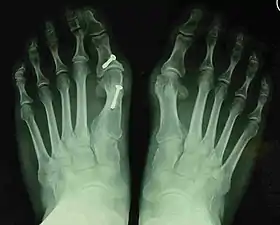

![]() Fig. 8a. Painful hallux valgus and metatarsus primus varus deformity recurrence of left foot after osteotomy surgery | |

- For recurrence correction after osteotomy procedure (Fig. 8)

Late deformity recurrence can happen after osteotomy (bone-breaking) procedures because osteotomy surgeries do not specifically stabilize first metatarsal bone.